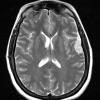

NEOPLASMS (MENINGIOMA)

Secretory (7)